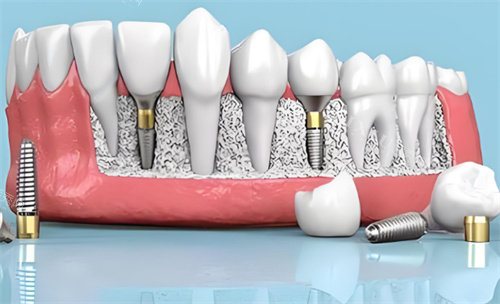

即刻种植能让缺牙患者快速修养牙齿功能与美观,无需经历漫长的缺牙等待期,因此成了不少人的首要选择。而种植体的设计是否适配即刻种植需求,直接影响手术结果。伊诺种植体凭借独特的仿生根型设计,在即刻种植中表现亮眼,这背后有 3 大关键理由支撑。

伊诺种植体的仿生根型设计是其核心优势之一。它参照天然牙根的形态弧度进行打磨,顶部呈圆钝的锥形,中部至底部逐渐过渡为柱状,与人体牙槽骨内的牙根生长轨迹高度契合。这种设计在即刻种植时,能顺着原牙根的骨槽方向植入,减少对周围骨组织的切削量 —— 传统柱状种植体植入时可能需要磨除部分健康骨质来调整角度,而伊诺种植体因形态适配,植入时的骨组织损伤率可降低 30% 左右。

同时,其表面的 “仿生螺纹” 也暗藏巧思。螺纹深度从顶部到底部逐渐加深,顶部浅螺纹能减少对牙龈下方薄弱骨组织的刺激,底部深螺纹则能增强与深层牙槽骨的咬合力,既保护了即刻种植时可能较为脆弱的牙龈边缘,又能快速获得初期固位,这对刚拔牙后的牙槽窝来说尤为重要。

即刻种植的核心要求之一是种植体能快速达到初期稳定,以便尽早安装临时牙冠实现即刻负重。伊诺种植体在这方面表现突出,其仿生根型设计搭配表面喷砂酸蚀技术,能在植入后 1 小时内实现初期稳定性 ISQ 值≥65(临床认为 ISQ≥60 即可满足即刻负重基础)。

这得益于两方面:一是仿生根型与牙槽窝内壁的贴合度更高,能通过 “形态锁合” 减少种植体微动;二是喷砂酸蚀处理形成的 2-3μm 微孔表面,可在短时间内吸附大量血小板和骨细胞,加速 “机械固位” 向 “生物固位” 过渡。临床数据显示,使用伊诺种植体进行即刻种植的患者中,92% 能在术后当天佩戴临时牙冠,且咀嚼软质食物时无明显松动感。

即刻种植后,种植体与牙槽骨的骨结合速度直接关系到成功概率。伊诺种植体虽采用常规喷砂酸蚀表面处理,但结合仿生根型设计后,骨结合效率有了明显提升。其仿生形态能引导骨细胞沿着种植体表面的弧度有序生长,避免传统直柱状种植体可能出现的 “骨生长方向紊乱” 问题。